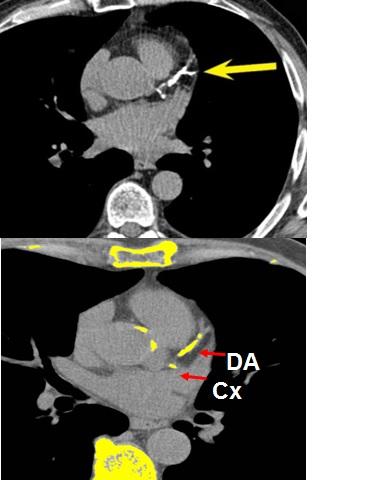

The JACC study shows a relationship between LDL-C levels that are considered healthy in current clinical guidelines and the extent of atherosclerosis in multiple vascular territories: the aorta and the carotid, iliofemoral, and coronary arteries. Using the latest noninvasive vascular imaging technology, the study demonstrates that "atherosclerotic plaques are present in 50% of middle-aged individuals (40-54 years old) with no classical cardiovascular risk factors: non-smokers with no hypertension, diabetes mellitus, or dyslipidemia. These findings could help to improve cardiovascular prevention in the general population even before the appearance of conventional risk factors, an example of primordial prevention," explained Dr. Leticia Fernandez-Friera.

This ambitious project was made possible through the shared commitment of the CNIC and Banco Santander and the leadership of principal investigator Dr. Fuster. The PESA study uses the latest noninvasive vascular imaging technology (magnetic resonance, PET, CT, and 2D and 3D ultrasound) in an attempt to answer important unresolved questions about cardiovascular disease: when and how it begins and what has to happen for it to manifest clinically. As study author Dr. Antonio Fernández-Ortiz explained, "Thanks to vascular ultrasound, we can directly visualize the presence of cholesterol plaques in the carotid arteries, the aorta, and the iliofemoral arteries; and with computed tomography, we can detect calcification in the coronary arteries. With these approaches, we are able to evaluate the progress of the disease in an individual."